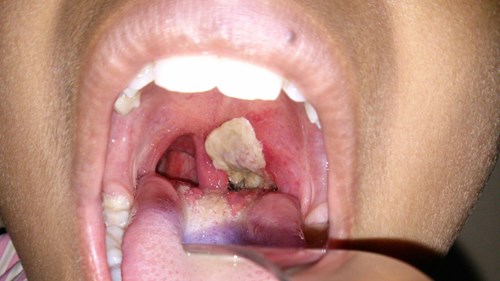

Triệu chứng của bệnh bạch hầu là sốt, viêm họng, chán ăn, xuất hiện giả mạc trắng ở hốc miệng; phòng ngừa tốt nhất là tiêm văcxin, nếu mắc bệnh cần giữ vệ sinh kỹ, theo bác sĩ Phan Lương Ánh Linh, Bệnh viện Đa khoa Tâm Trí Sài Gòn.

Để kịp thời ứng phó với dịch bạch hầu tại Bình Phước, ngăn chặn nguy cơ lây lan và bùng phát dịch, Bộ Y tế đã khẩn trương chỉ đạo Viện Vắc xin và Sinh phẩm y tế xuất 10.000 liều vắc xin Td phòng chống dịch bạch hầu.

Bệnh bạch hầu gần như “biến mất” trong các năm gần đây, tuy nhiên mới đây tại Bình Phước đã xuất hiện bệnh, khiến 3 người tử vong, 29 người nhập viện. Bộ Y tế đã vào cuộc để ngăn chặn dịch bệnh lây lan.